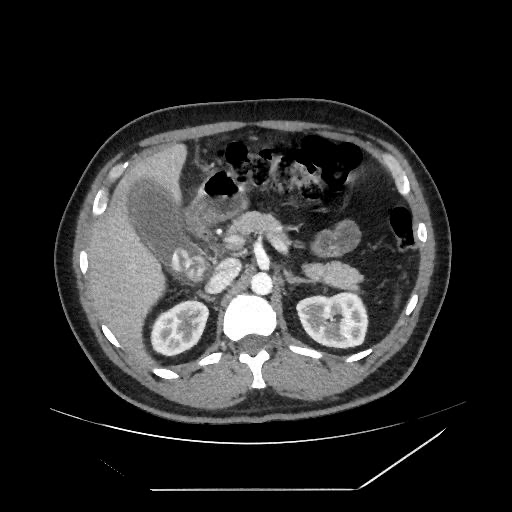

Tomografia computadorizada

A tomografia computadorizada (TC) é um exame de imagem mais detalhado e pode ser útil na avaliação de condições como a colecistite aguda, tumores das vias biliares e outras condições hepáticas. Pode ser usado de maneira contrastada ou não.

A neoplasia das vias biliares pode afetar os ductos biliares e a vesícula biliar. Os principais fatores de risco para o desenvolvimento incluem a idade avançada, o sexo masculino, a presença de cálculos biliares, a colangite esclerosante primária e outras doenças hepáticas crônicas. O diagnóstico é feito pela USG abdominal, tomografia computadorizada e ressonância magnética, além da biópsia de tecido hepático. O tratamento envolve cirurgia, radioterapia, quimioterapia ou a combinação desses métodos.